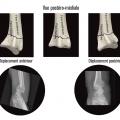

Au niveau métaphysaire le déplacement peut être postérieur ou antérieur (fig. 6). En ce qui concerne le déplacement postérieur, il est important de se souvenir que la surface articulaire regarde vers l’avant. En d’autres termes, dès que cela n’est plus le cas, même si la surface articulaire n’est pas orientée vers l’arrière, il s’agit d’un déplacement postérieur. Classiquement, le déplacement postérieur est lié à un mécanisme dit en compression-­extension, c’est-à-dire une chute sur la main, le poignet étant en extension (fig. 7). Le déplacement est dit antérieur s’il y a une exagération de l’orientation antérieure de l’épiphyse radiale. Ce déplacement est classiquement lié à un mécanisme dit en compression-flexion, c’est-à-dire une chute sur la main, le poignet étant en flexion (fig. 7). La plupart du temps, ce déplacement postérieur ou antérieur s’accompagne également d’un déplacement externe, avec un tassement au niveau de la corticale latérale (fig. 8). Outre le déplacement antérieur, postérieur ou latéral, il est très important d’analyser au niveau du foyer de fracture métaphysaire l’importance de la comminution qui peut être uniquement postérieure, ou antérieure, ou circonférentielle, ce qui conditionne la stabilité de la fracture et oriente vers le type d’ostéosynthèse à réaliser.

La mise en place des broches percutanées sont habituellement introduites dans le foyer de fracture, en arrière du radius, puis inclinées vers le bas pour réduire la bascule dorsale de la glène radiale et sont finalement fichées dans la corticale antérieure, épaisse, pour stabiliser la réduction obtenue. Il s’agit d’un embrochage « intrafocal » (dans le foyer de fracture). Une ou deux broches styloïdiennes dans le plan frontal complètent le montage. La bascule antérieure du fragment distal, la présence de refends articulaires, et la comminution métaphyso-épiphysaire sont indispensables à évaluer avant de proposer ce type de traitement et constituent des contre-indications relatives (fig. 12).

La mise en place de plaques palmaires nécessite un abord chirurgical antérieur et reste techniquement délicat, en particulier pour positionner la plaque en hauteur et pour la longueur des vis dont l’excès peut endommager les tendons extenseurs. L’indication phare reste les fractures métaphysaires à déplacement antérieur ou les comminutions métaphysaires étendues (fig. 13).